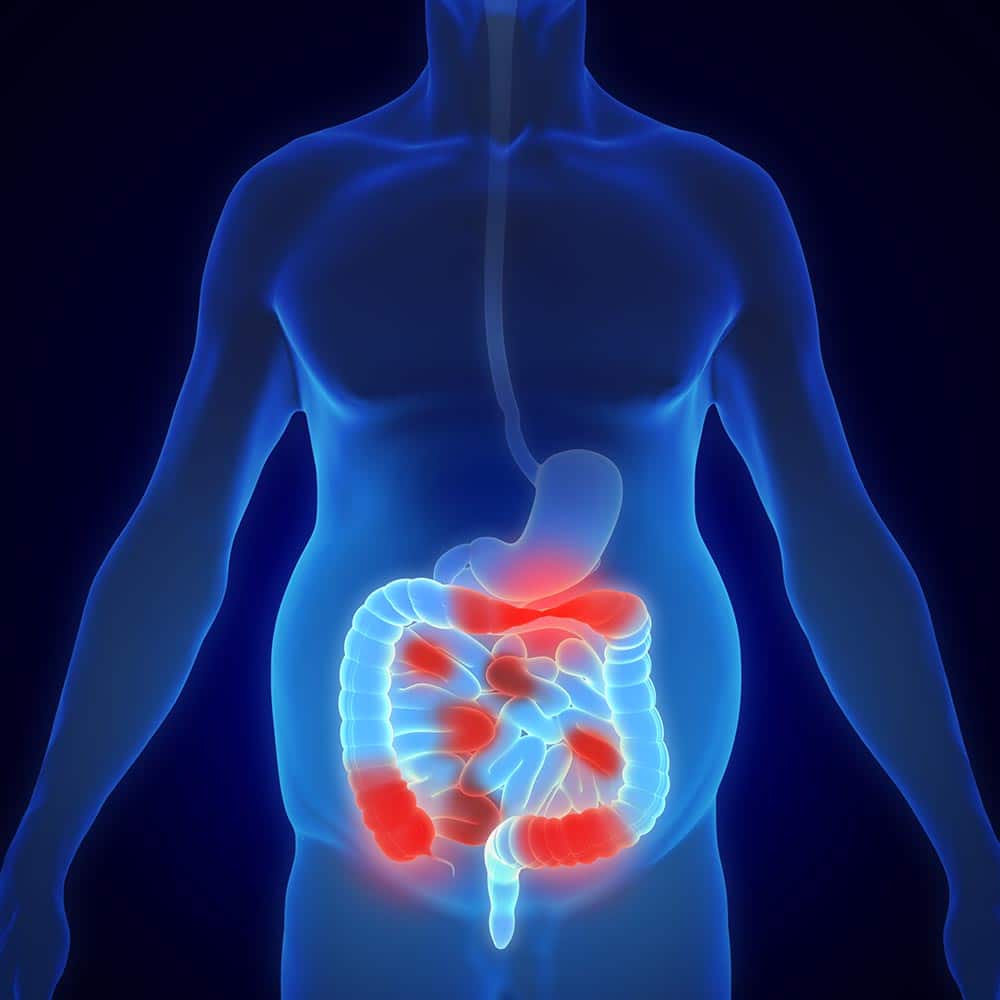

Chronic IBD

What are chronic inflammatory bowel diseases?